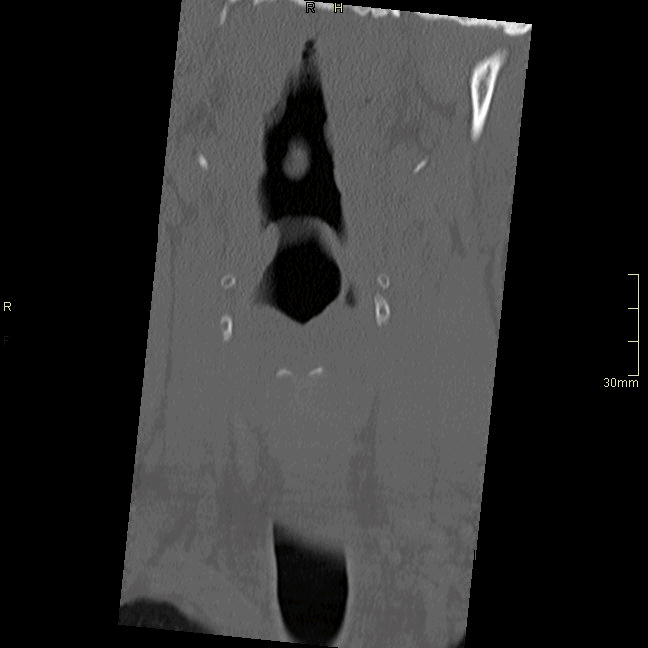

CT Cervical Spine Non Contrast- Bone window (coronal)

CT Cervical Spine Non Contrast- Soft Tissue window (coronal)